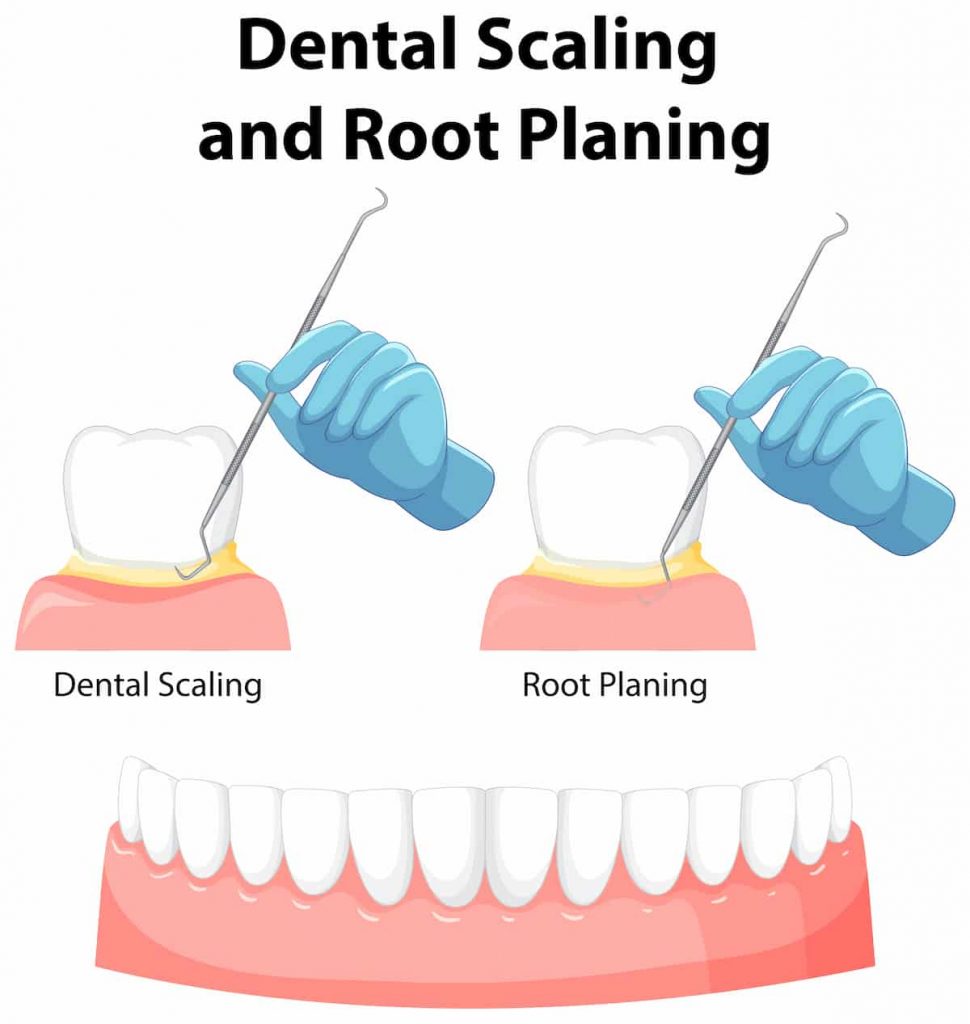

The treatment for itchy gums will depend on the cause of the problem. For instance, if your gums are itchy due to poor oral hygiene, your dentist might recommend scaling and root planing.